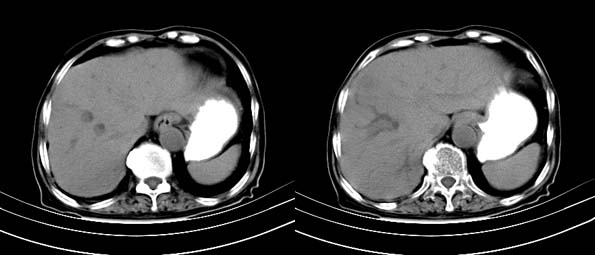

以下是引用bailaode在2008-6-12 22:10:00的发言:[br]资料中未提及患者有无急腹症体征,这个很重要。[br] ct表现:肝内境界模糊之低密度灶,内有含对比剂之液气平面.(提示肝内病灶与胃肠道沟通) [br] 1、根据“长城干红 ”所提供的资料“患者,女,74岁,黑便月余,消瘦,一般状况差,白细胞1万四千”,是否可认为是个慢性病程?那么我首先考虑:十二指肠结核,十二指肠--胆管瘘,继发胆道逆行感染肝脓肿形成。[br] 2、如有急腹症体征则考虑:十二指肠溃疡穿孔?十二指肠占位伴穿孔?

以下是引用拾荒者在2008-6-13 22:13:00的发言:[br]病灶与升结肠、肝脏及十二指肠关系密切,且结肠降段见造影剂影,支持结肠与十二指肠瘘形成,原因及原发病在哪不好定,不过,虽说有风险,但还是应该手术治疗,单纯抗感染估计不行。